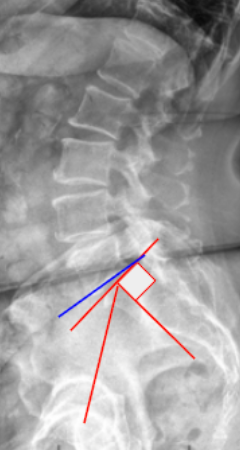

2) Instructions to Measure

• Obtain a standing lateral lumbosacral X-ray including the pelvis, sacrum, and L5 vertebra.

• Identify key anatomic landmarks:

• Center of the femoral heads (midpoint if both visible).

• Center of the S1 superior endplate.

• Inferior endplate of L5 and superior endplate of S1.

• Measure Pelvic Incidence (PI):

• Draw a line connecting the center of the femoral heads to the center of the S1 endplate.

• Draw a line perpendicular to the S1 endplate.

• The angle between these two lines is the Pelvic Incidence (PI).

• Measure Slip Angle (Lumbosacral Kyphosis Angle):

• Draw a line along the inferior endplate of L5.

• Draw a line along the superior endplate of S1.

• Measure the angle between these lines, which represents the Slip Angle.